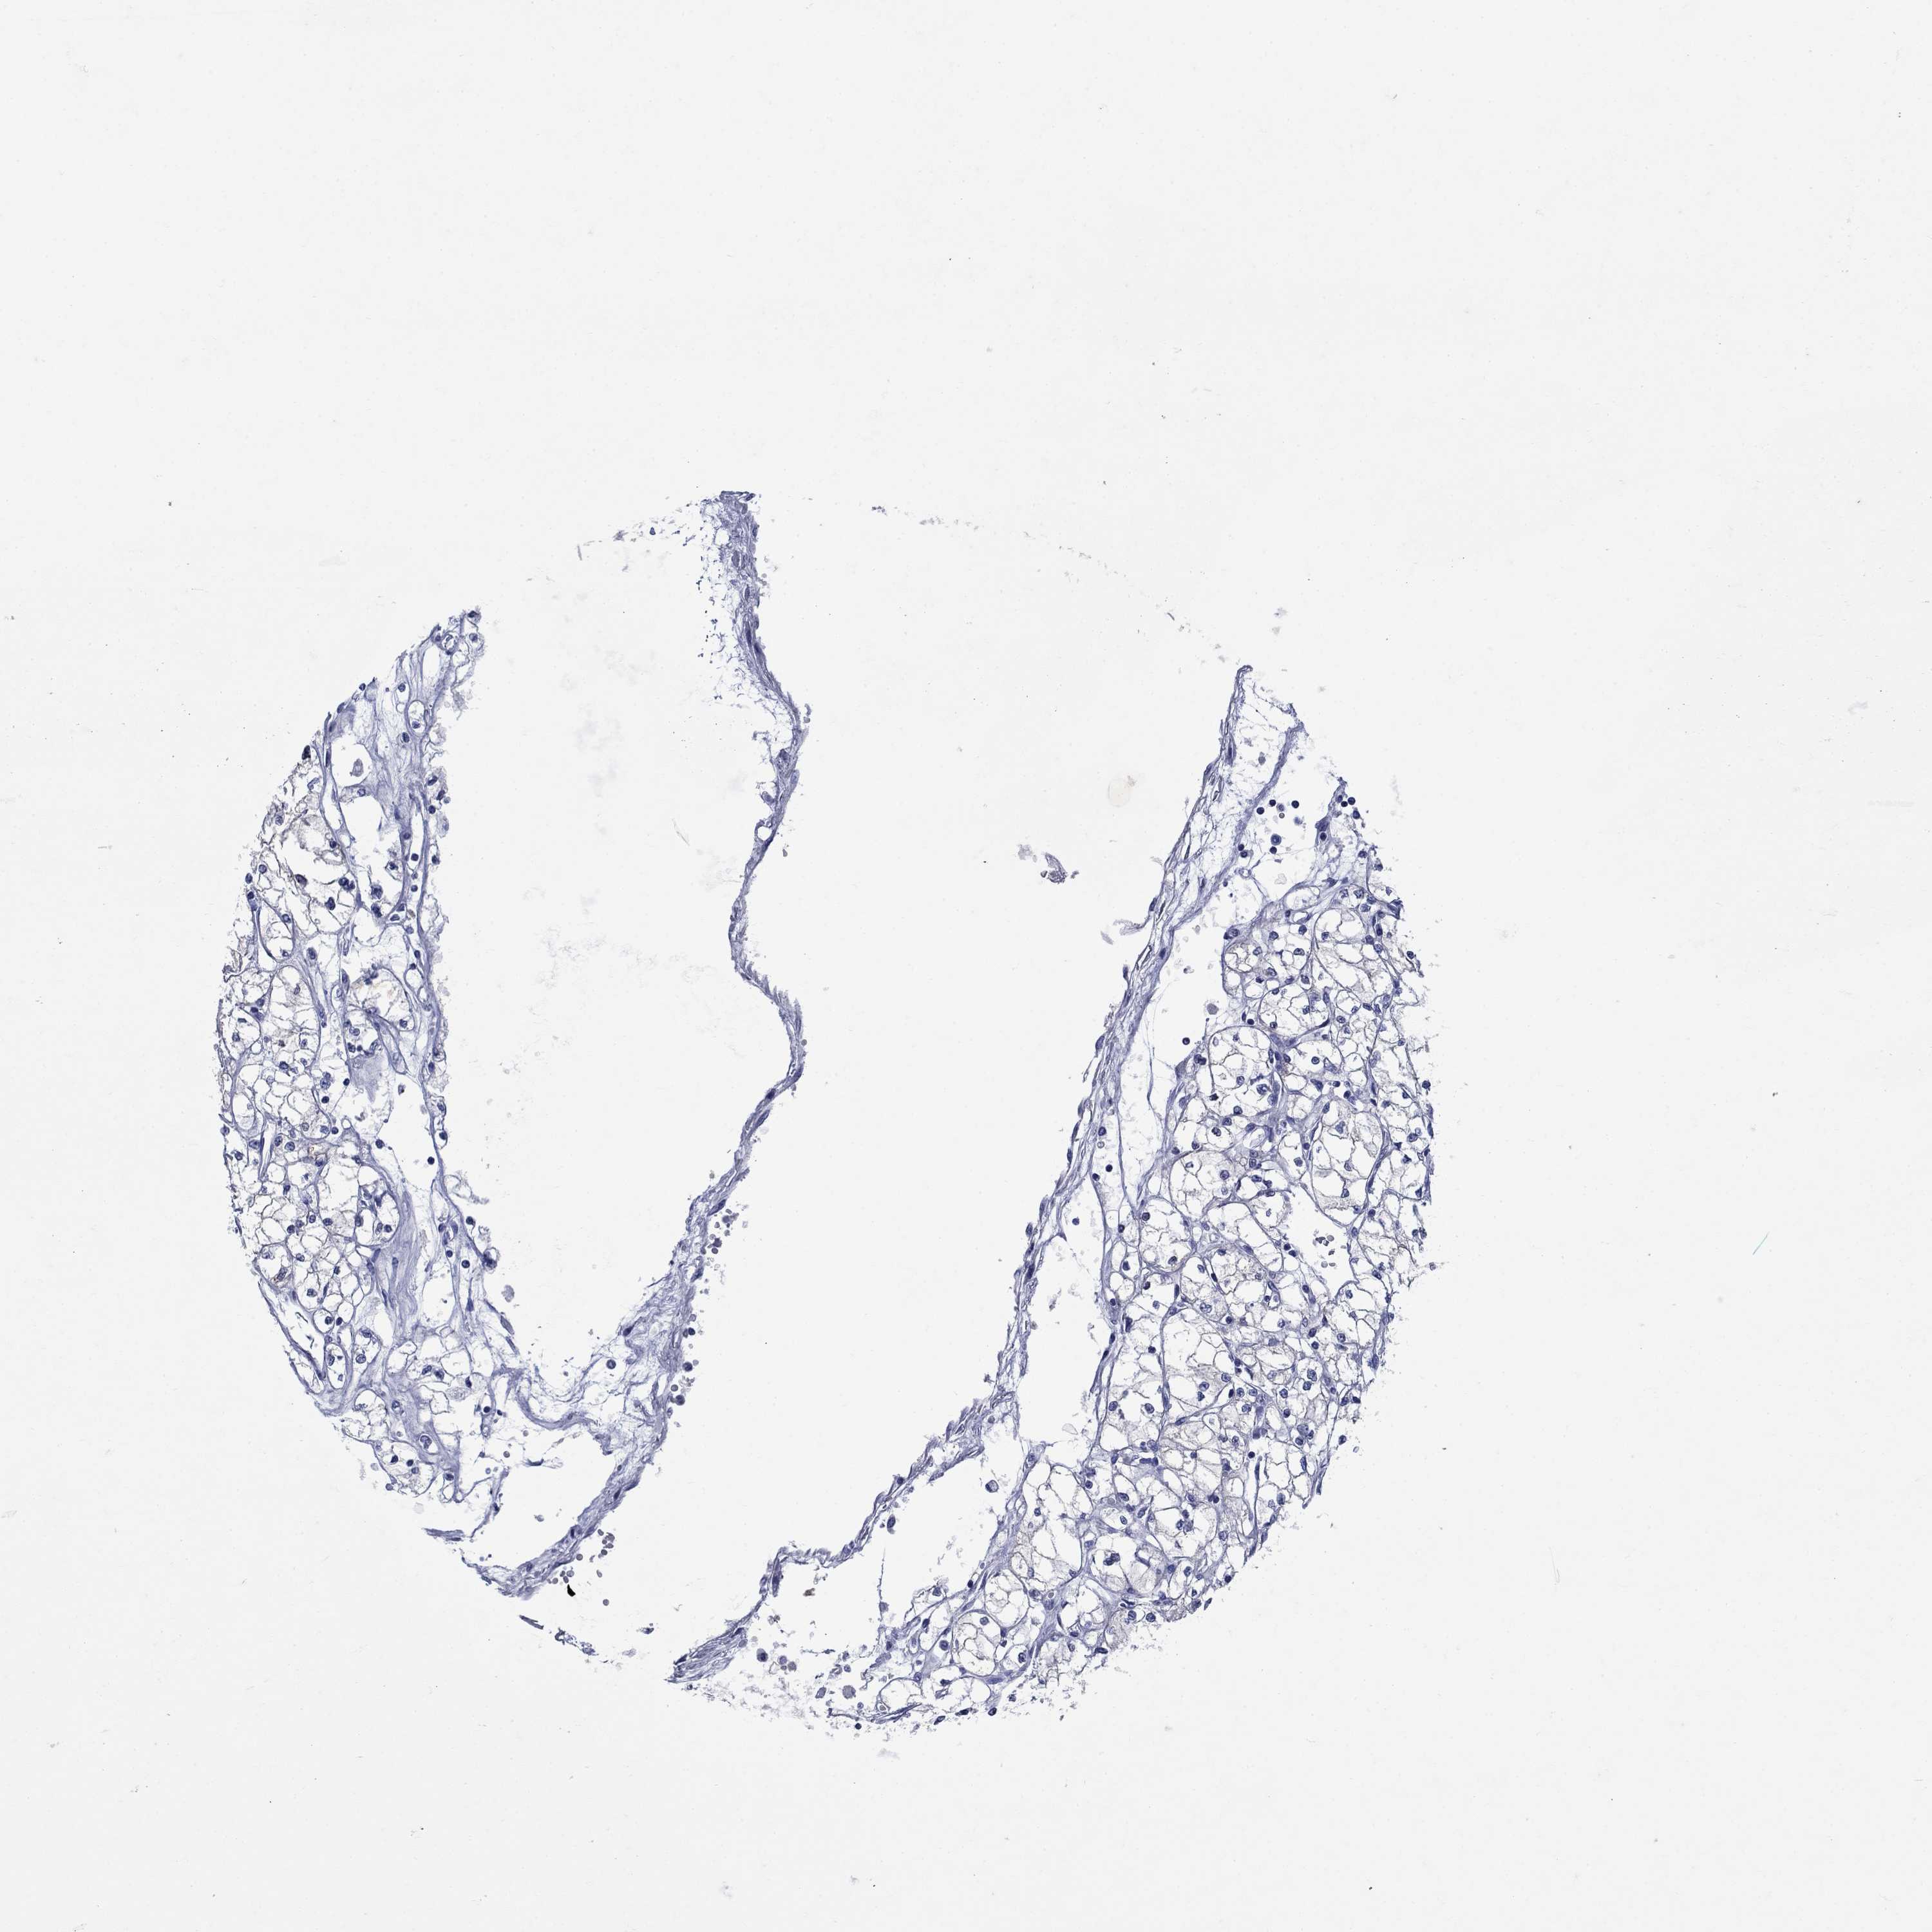

Renal cancer

Kidney chromophobe